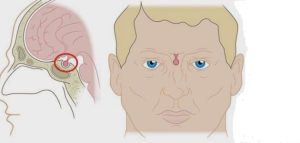

- ومن الأعراض الشائع حدوثها لورم الغدة النخامية هي فقدان جزء من مجال الرؤية للشخص المصاب.

- من أكثر المضاعفات شيوعًا لورم الغدة النخامية هي فقدان الرؤية، حيث أن تلك الغدة تقع في مكان تقابل عصبي العينين، ومع ضغط الورم على أعصاب الرؤية، يحدث خلل في وظيفتها.